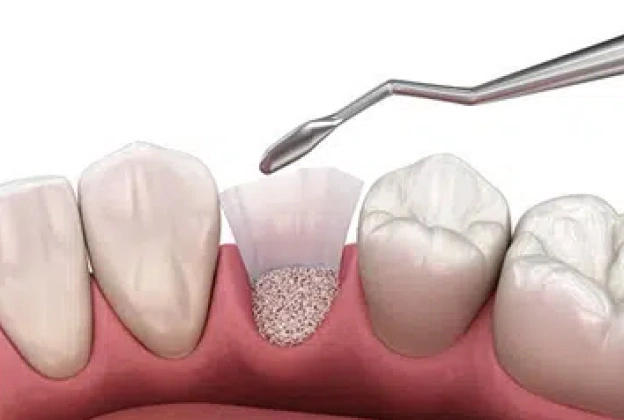

- Performed using minimally invasive surgical techniques for quicker recovery